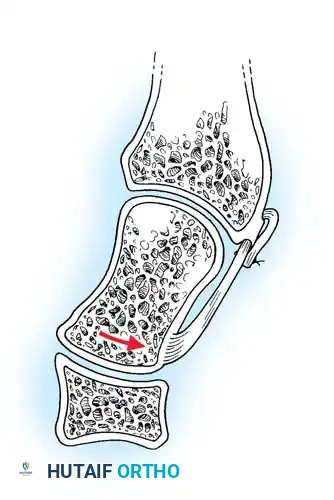

- Joint Preparation: The dorsal cartilage of the radiocarpal, intercarpal, and third carpometacarpal joints is meticulously denuded down to bleeding subchondral bone.

- Bone Grafting: A local distal radial bone graft portal is utilized. Cancellous bone is harvested from the distal radius metaphysis to augment the fusion sites.